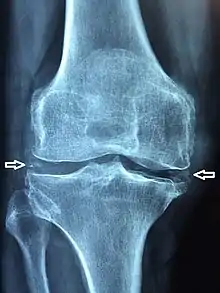

La chondrocalcinose articulaire (CCA) est une arthropathie microcristalline caractérisée par la précipitation de cristaux de pyrophosphate de calcium dihydraté (en) dans les tissus articulaires et périarticulaires. Elle entraîne la formation de calcification intra-articulaire sous la forme d'un liseré opaque fin, cernant les contours articulaires à quelques millimètres de l'os sous-chondral.

La forme pseudo-arthrosique représente 50 % des cas. Plus sévère que l’arthrose classique, la clinique est marquée par des arthralgies chroniques de types mécaniques et les radiographies montrent des signes classiques d’arthrose associés à des liserés typiques de la chondrocalcinose dans le cartilage et dans le fibrocartilage (les ménisques par exemple). Les articulations les plus souvent touchées sont la scapho-trapézienne, le poignet, les chevilles et les métacarpo-phalangiennes[3].